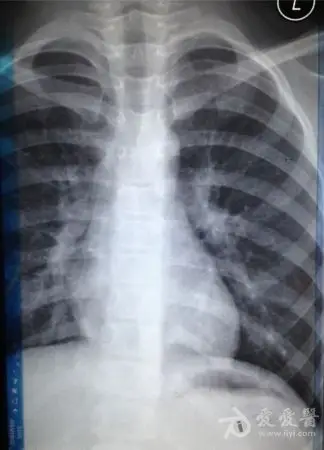

这几组患儿胸片是肺炎还是正常影像规培医师懵了

小孩四岁发烧不退诊断为肺炎,帮忙看下两次片子是否好了

新生儿肺部常见疾病的x线诊断2 新生儿感染性肺炎 男,3天.